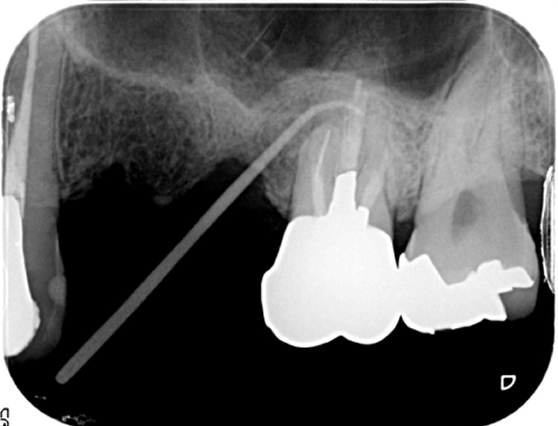

根管治療 症例4

抜歯と言われたが、抜歯する必要があるか診てほしい

破折ファイルの残存を認めるが抜歯と診断する所見がなかったため根管治療を提案。

根管治療で破折ファイルを除去。経過観察2年で良好な経過と治癒を確認